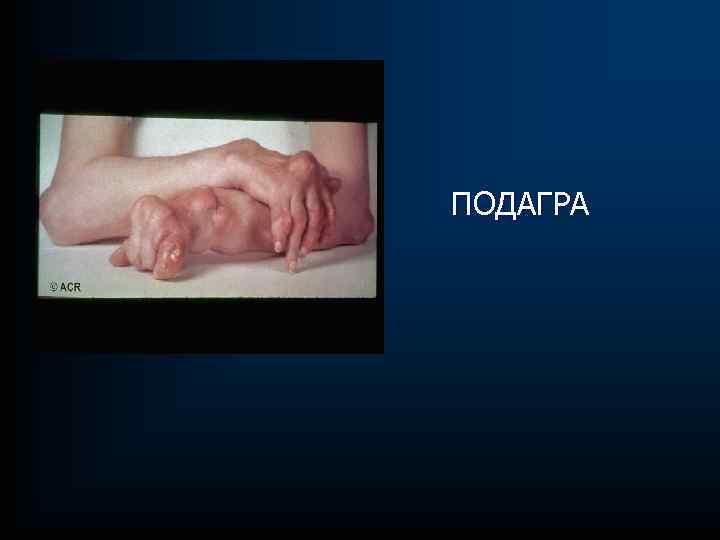

ПОДАГРА

ПОДАГРА

ПОДАГРА – это системное тофусное заболевание, развивающиеся в связи с воспалением в месте отложения кристаллов моноурата натрия или мочевой кислоты у людей с гиперурикемией, обусловленной внешнесредовыми и/или генетическими факторами

ПОДАГРА – это системное тофусное заболевание, развивающиеся в связи с воспалением в месте отложения кристаллов моноурата натрия или мочевой кислоты у людей с гиперурикемией, обусловленной внешнесредовыми и/или генетическими факторами